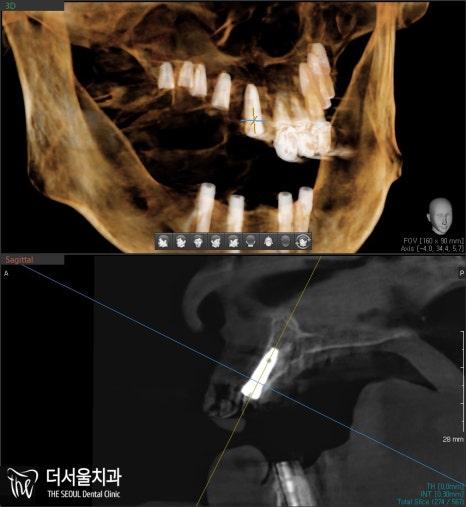

수술을 진행하기 앞서

CBCT와 네비게이션 가이드를 이용하여

정밀 검사를 선행해줍니다.

산성역치과 에서 확인한 결과,

전반적으로 골폭이 좁은 상태였습니다.

픽스처를 심는다 하더라도

튼튼한 고정력을 갖추기 어렵습니다.

때문에 뼈이식을 진행하기로 합니다.

픽스처를 심을 수 있을 정도로

깊이는 충분했습니다.

그러나 옆을 보면 폭은 충분치 않죠.

따라서 옆 부분에 뼈 재료를

아낌없이 넣어드려서

두꺼운 골폭을 형성했습니다.